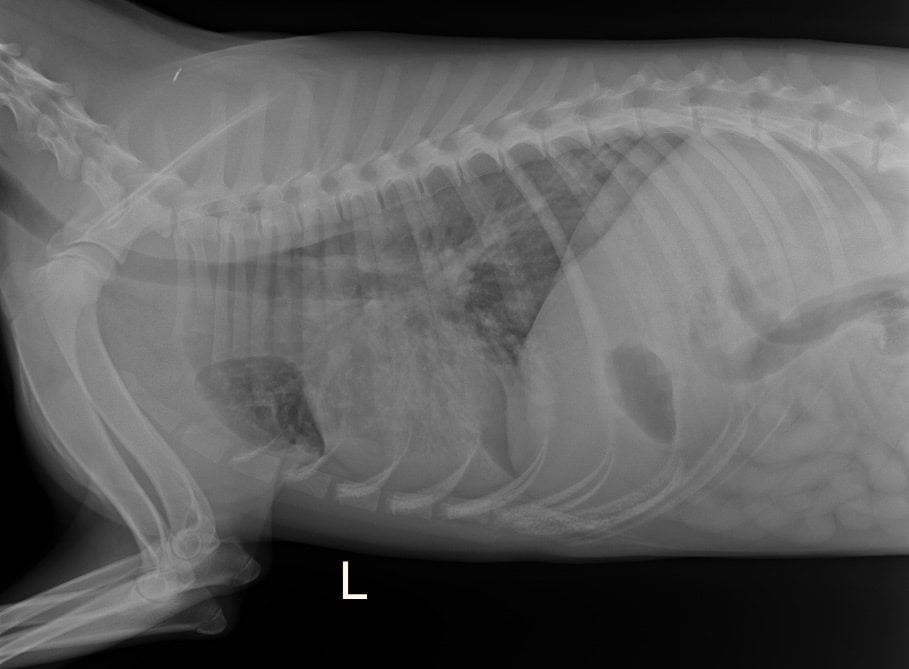

FENRIK ist ein wunderbarer, toller Hund, freundlich, liebenswert und einfach ein toller Gefährte. Leider bringt er gesundheitliche Probleme mit, die nicht zu unterschätzen sind. Laut unserer Tierärztin handelt es sich bei ihm um einen medizinischen Notfall. Bereits als Welpe hatte FENRIK wiederholt mit Lungenerkrankungen zu kämpfen. Es ist daher wahrscheinlich, dass seine Lunge dauerhaft geschädigt sein könnte oder dass er zumindest immer wieder anfällig für Lungenentzündungen bleibt.